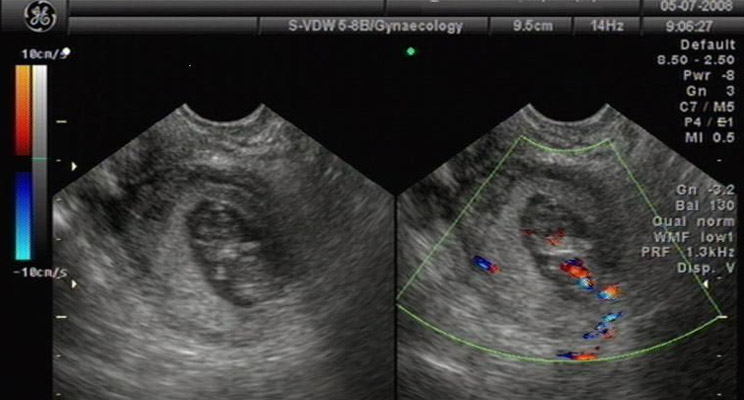

3、B超诊断:宫腔内未探及妊娠囊,若宫旁探及异常低回声区,且见胚芽及原始心管搏动,可确诊异位妊娠。若宫旁探及混合回声区,子宫直肠窝有游离暗区,虽未见胚芽及胎心搏动,也应高度怀疑异位妊娠。

将血hCG测定与超声检查相配合,对异位妊娠的诊断帮助很大。当血hCG>2000IU/L、阴道超声未见宫内妊娠囊时,异位妊娠诊断基本成立。